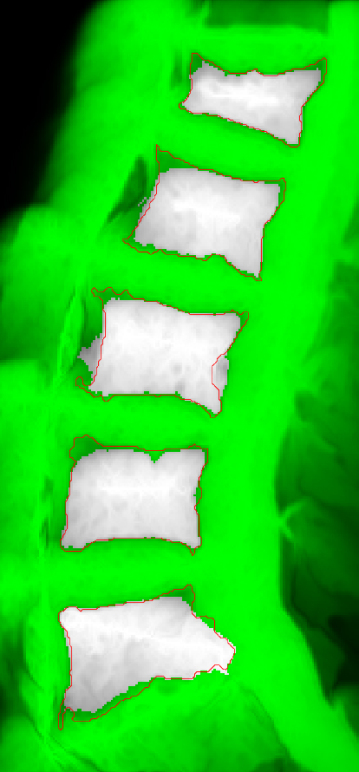

Comparing our proposed BGrowth (BG) to GrowCut (GC), in general, BG keeps similar recall and achieves better precision, consequently, a higher F-measure. Figure 6 shows the segmentation results for BGrowth, GrowCut and LazySnapping in a case with three benign VCFs in L1, L3 and L5 (L2 and L4 are normal). Note that, the dark and bright regions within the same vertebral bodies difficult the segmentation for all methods, presenting spiked borders due to the neighbours structure intensities, which are very similar (dark). On these cases, even the manual segmentation is challenging and requires much experience of the human operator.

BG generated smother and more delineated borders, which are closer the ground-truth. The LS also produced promising results. However, sometimes it fails to delimit borders when the interior annotation is closer to the ground-truth and the exterior annotation is not, as shown in results for L4 in Figure 6.

![]() |

| (a) GT and Annotations | (b) BGrowth (BG) | (c) GrowCut (GC) | (d) LazySnapping (LS) |